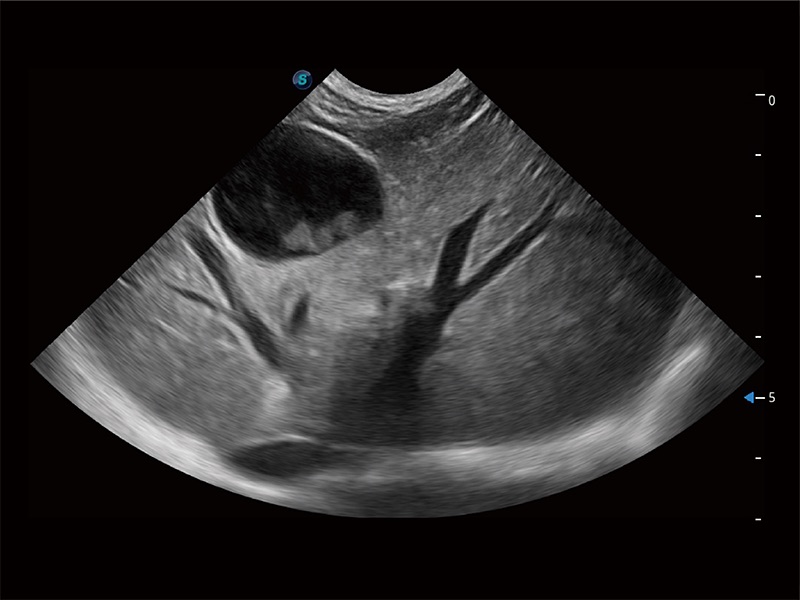

优异的基础图像

ProPet 80 全新的动物超声智能软件和丰富的探头群,为动物医生提供了高清晰度和精细分辨率的图像,无论在宠物、马科、畜牧还是实验室动物等应用中都可以轻松应对,为您的日常工作带来满意的体验。

(犬)胎儿四腔心